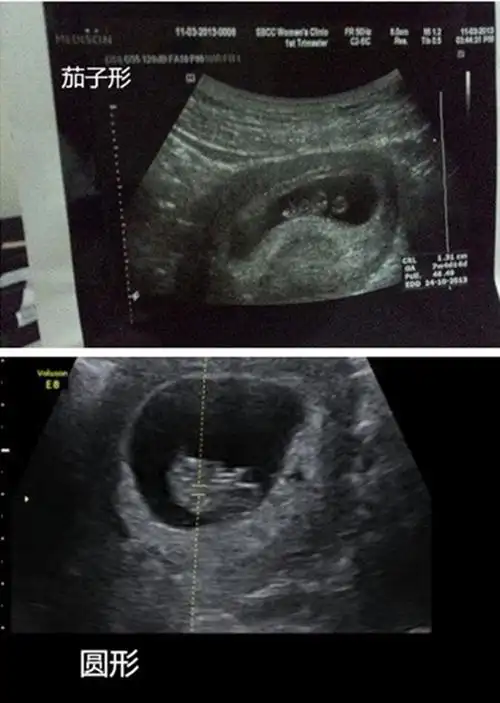

b超单子看男孩女孩1,看形状怀孕50天左右,b超孕囊形状是长形,像一个长